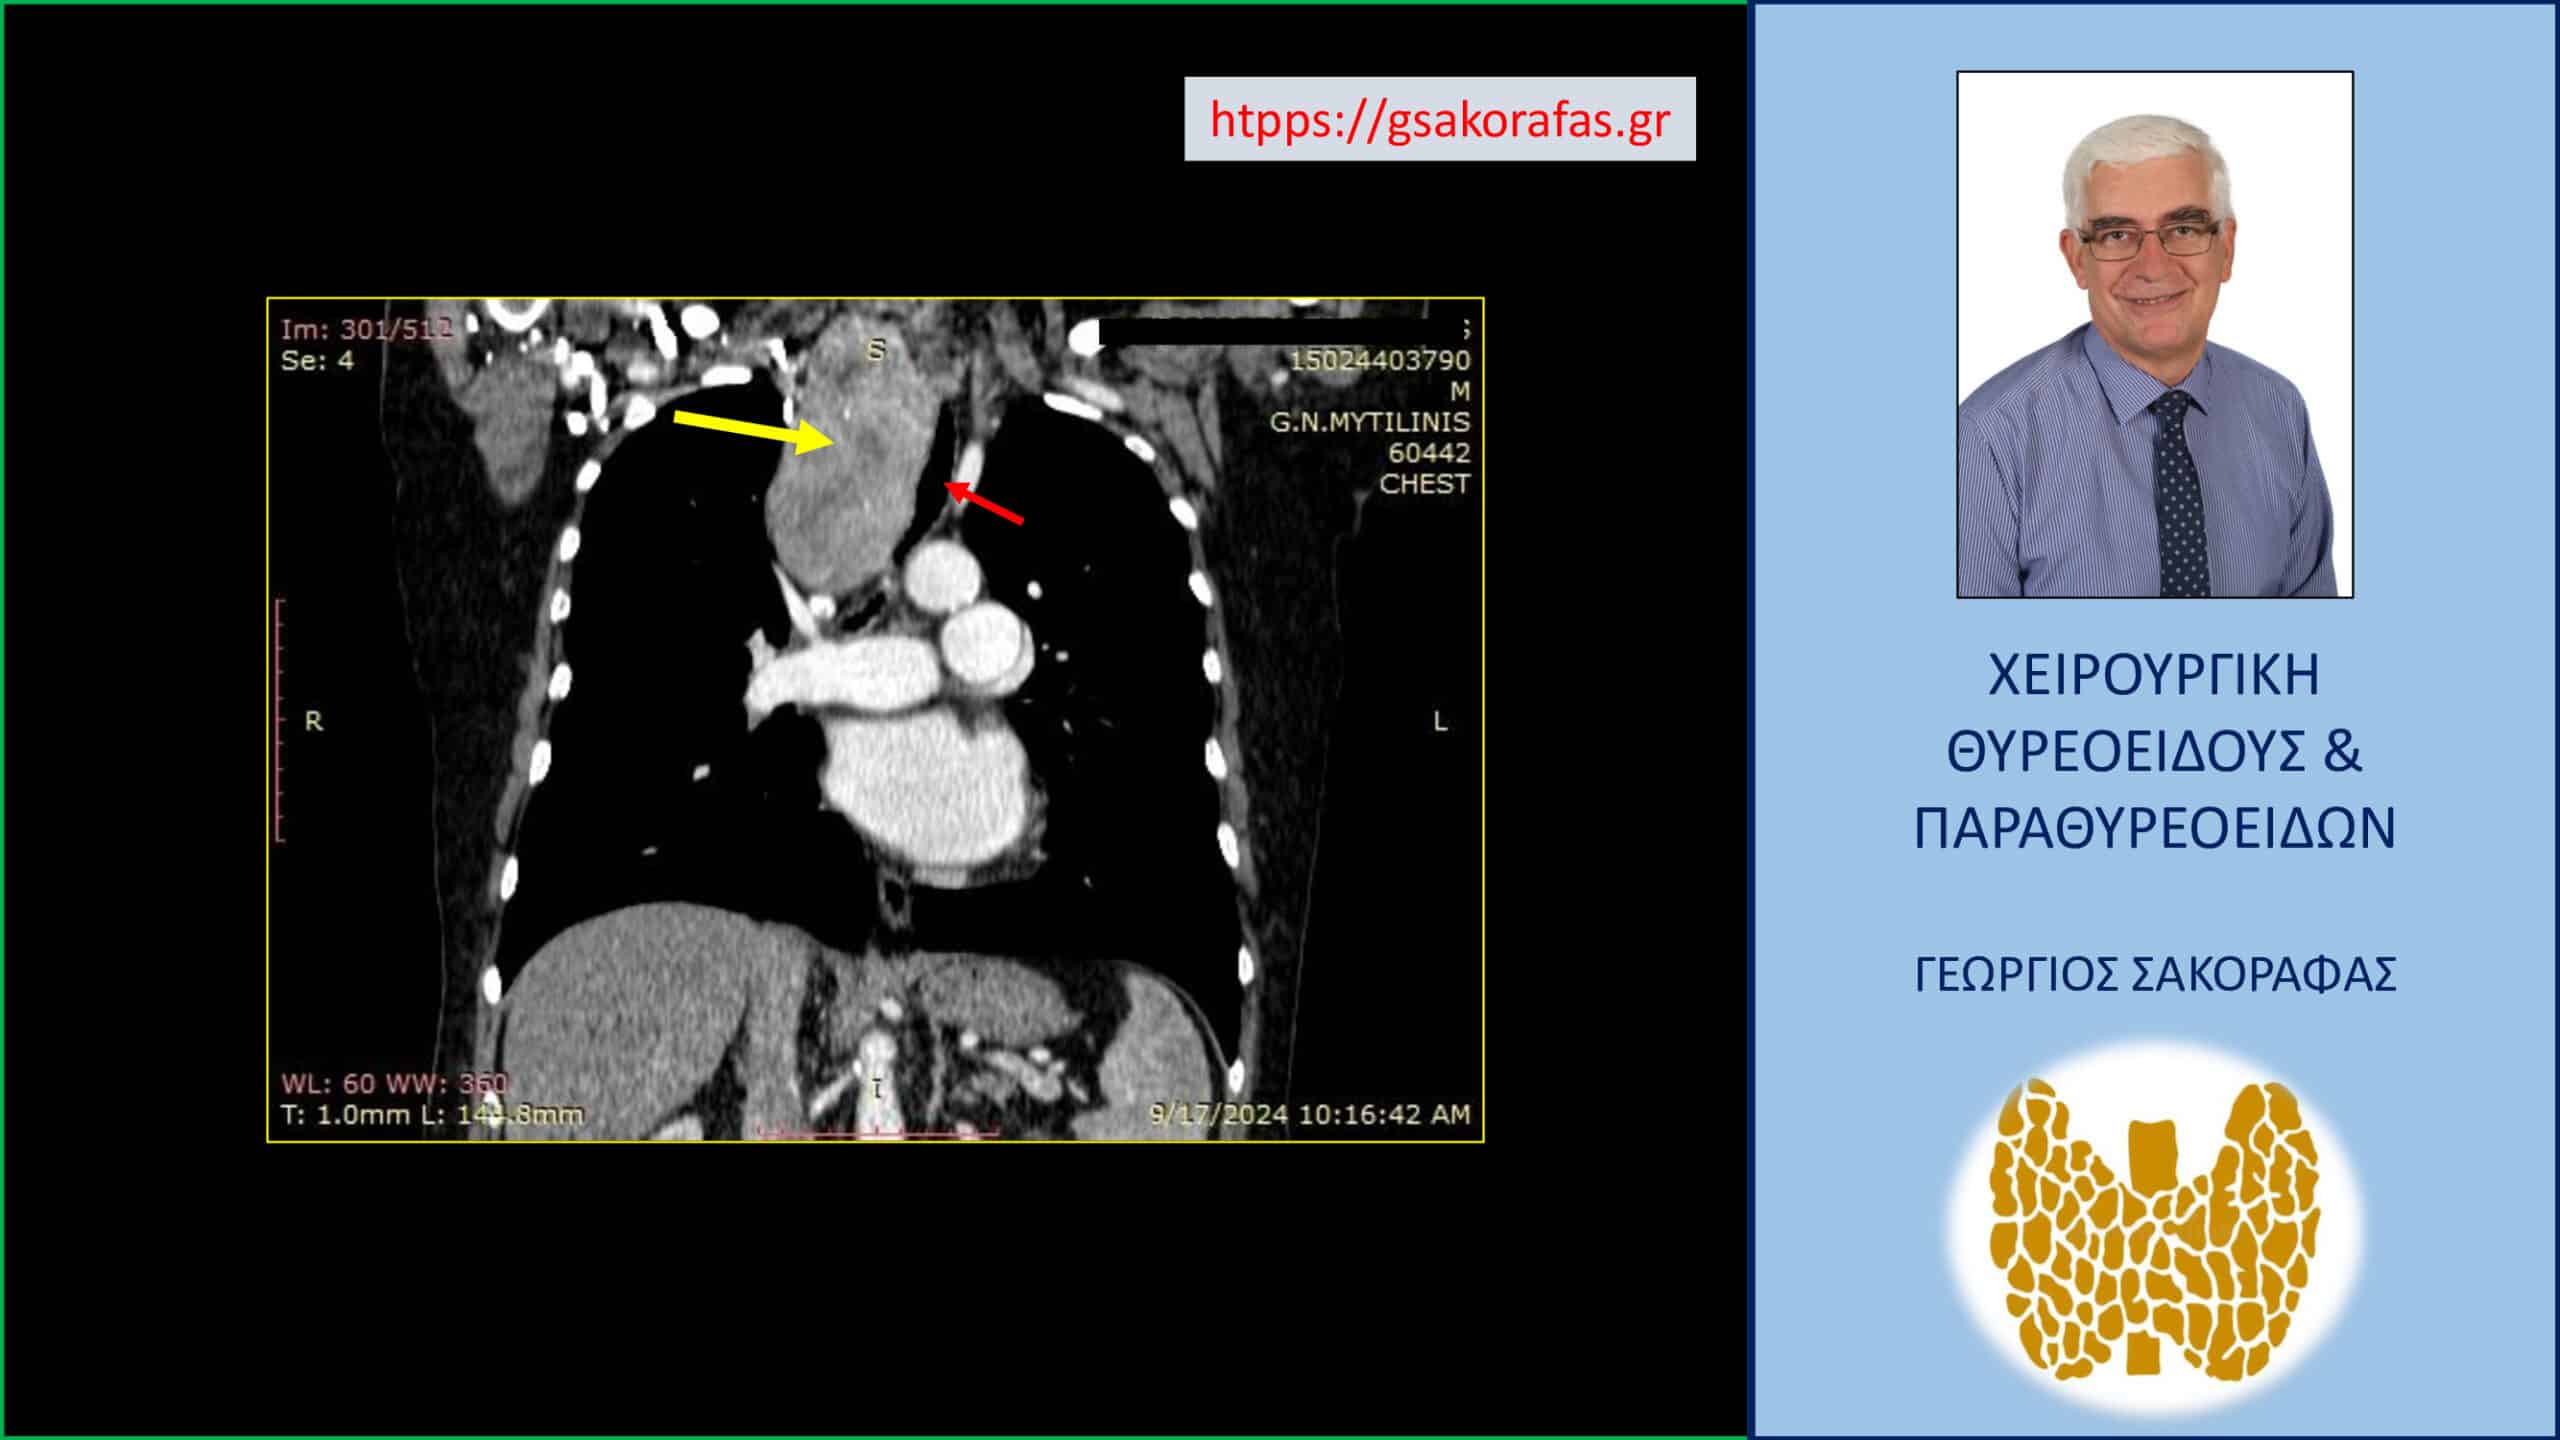

Καταδυόμενη βρογχοκήλη – απεικόνιση στην αξονική τομογραφία σε κατά μέτωπο διατομή. Εμφανής η πολύ μεγάλου βαθμού διόγκωση του δεξιού λοβού του θυρεοειδούς (κίτρινο βέλος) και η κατάδυσή του σε μεγάλο βάθος στην κοιλότητα του θώρακα, περίπου μέχρι τη μεσότητά του, στο ύψος του διχασμού της τραχείας (κόκκινο βέλος).